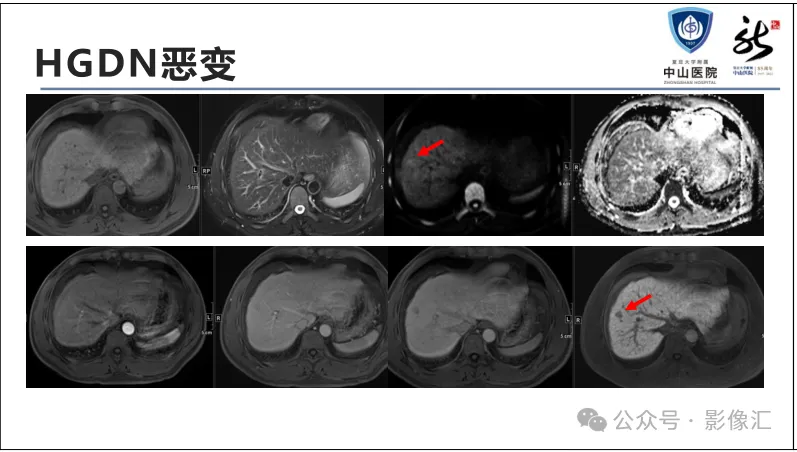

肝胆特异性对比剂增强肝胆图像判读方法与策略,课件来源于网络,作者复旦大学附属中山医院放射科饶圣祥教授。